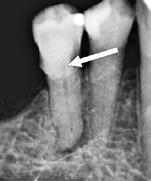

Fig. 13. Røntgenoptagelse af ikkefærdigdannet permanent tand efter traume.

A. Påvisning af rodresorption på 1+ (pil). B. Inkomplet rodudvikling. C. Periapikal læsion på 1+ og pulpaforkalkning og rodresorption på +1. Fig. 13. Radiograph of an immature permanent tooth after traumatic injury. A. displaying root resorption on maxillary right central incisor (arrow).

B. Incomplete root development. C. Periapical lesion on maxillary right central incisor and pulp calcification and root resorption on left central incisor.